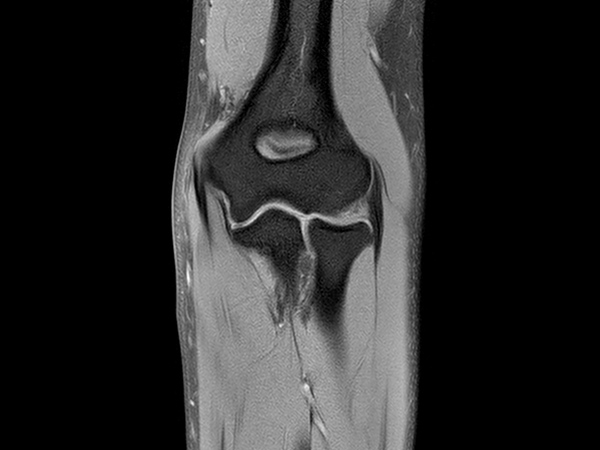

High quality Elbow imaging with Compressed SENSE

Spital Uster, Switzerland